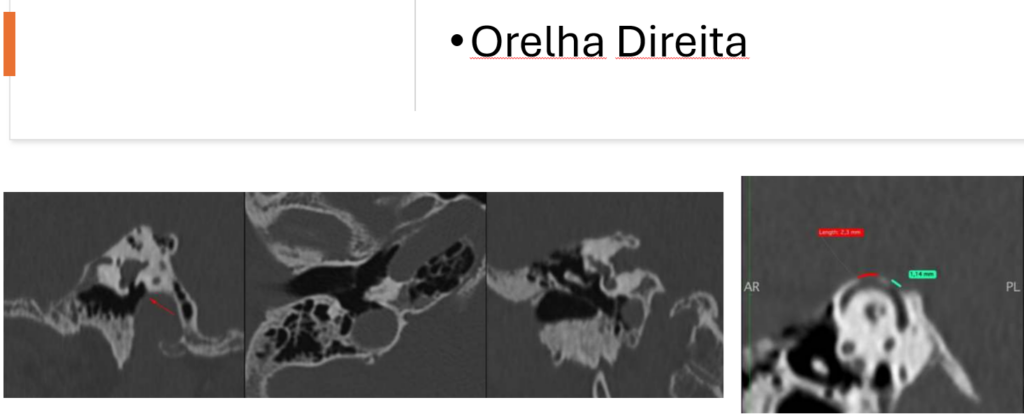

Na orelha direita observam-se dois focos de deiscência da limitante superior do canal semicircular superior que mede cerca de 2,3

mm e 1,1 mm.

Além disso: Bulbo jugular algo e proeminente, protruindo no hipotímpano, com foco deiscência (seta vermelha).